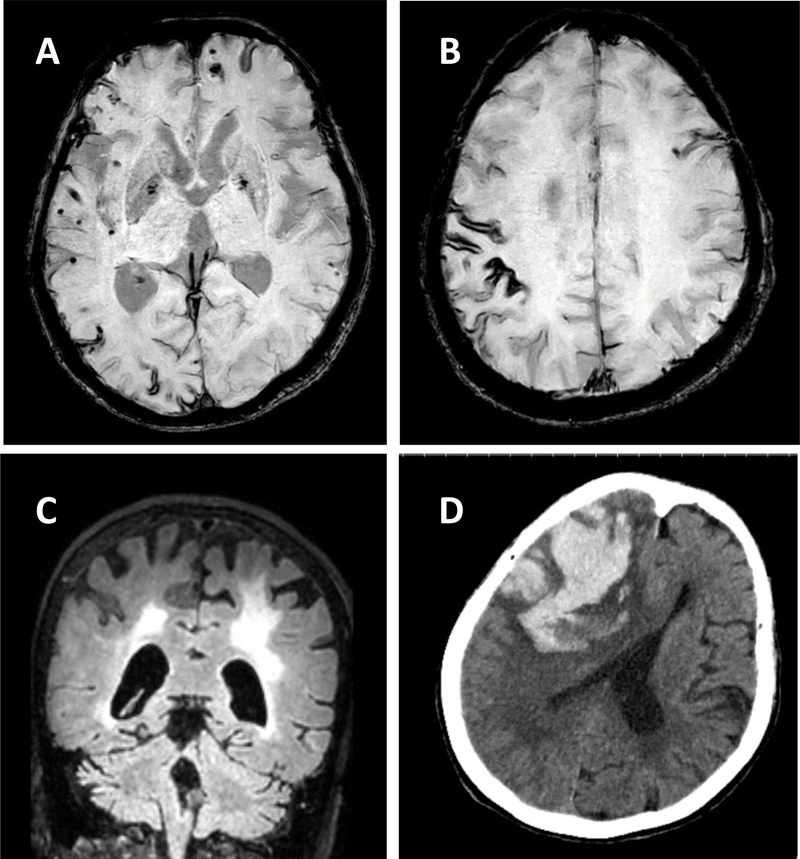

This work examined the enlargement of the perivascular space (PVS) in patients with cerebral amyloid angiopathy (CAA), an increasingly common form of cerebral small vessel disease. CAA is a common cause of lobar hemorrhage, cortical microhemorrhages and white matter disease in the elderly (Figure 3). In CAA, Aβ accumulates in the walls of cortical and leptomeningeal arteries, resulting in a loss of smooth muscle cells and impaired vascular function and can lead to lobar intracerebral hemorrhage in the elderly. The presence of cerebral vascular amyloid is a common neuropathological feature in patients with AD. PVS are compartments surrounding cerebral blood vessels that become visible on MRI when enlarged. It has been suggested that these spaces enlarge when there are deficits in dysfunctional perivascular clearance of waste products from the brain, including amyloid. The presence of enlarged PVS (EPVS) on MRI is associated with aging, high blood pressure, stroke and cognitive decline in other studies.

Figure 3. MRI and CT scan imaging of a 73-year-old woman with pathogenically confirmed cerebral amyloid angiopathy. Panel A shows innumerable cortical microhemorrhages, Panel B demonstrates cortical siderosis (GRE), and Panel C (FLAIR) shows extensive white matter disease and cerebral atrophy. Panel D is a CT scan taken 3 months after her prior MRI, when she presented with left hemiparesis and mental status changes. A large lobal hemorrhage is seen in the right frontal area, along with mass effect and cerebral edema.

In this paper (10) the authors used 3T and 7T ex vivo MRI, semi-automatic segmentation and validated deep-learning-based models to quantify EPVS and associated histopathological abnormalities in 19 CAA cases and 5 controls. Severity of MRI-visible PVS during life was significantly associated with the severity of MRI-visible PVS on ex vivo MRI. This also corresponded with PVS enlargement on histopathology in the same areas. EPVS were located mainly around the white matter of perforating cortical arterioles. The amount of EPVS was associated with CAA severity in the overlying cortex. In addition, the authors found markedly reduced smooth muscle cells and increased vascular Aβ accumulation, extending into the WM, was seen in individual affected vessels with an EPVS. The presence of Aβ was also observed in the WM portion of the same perforating vessels, decreasing in intensity with increasing distance from the cortex. This could reflect blockage of Aβ clearance towards the brain surface, consistent with the decreasing severity of CAA between superficial and deep cortical layers, as previously shown histologically. These findings were confirmed in a patient with hereditary amyloid that was much younger (Dutch mutation). These findings are consistent with the concept that the development of EPVS reflects impaired outward flow along arterioles. This has implications for other small vessel diseases and suggests the importance of perivascular clearance mechanisms in human brain, which play an important role in the pathophysiology of both CAA and AD. These results support the concept of outward flow along the walls of cortical arterioles and suggest that impaired perivascular clearance of Aβ might lead to fluid stagnation and PVS enlargement around upstream portions of connected perivascular compartments. Interestingly, removal of Aβ plaques with anti-Aβ immunotherapy can worsen cortical and leptomeningeal CAA (11), suggesting that after plaque disaggregation Aβ is cleared along the cerebral vessels. Considering the currently unknown role of EPVS and white matter hyper-intensities (WMHs) and what they signify in humans both with and without AD/CAA, this paper has important clinical and pathophysiological relevance.